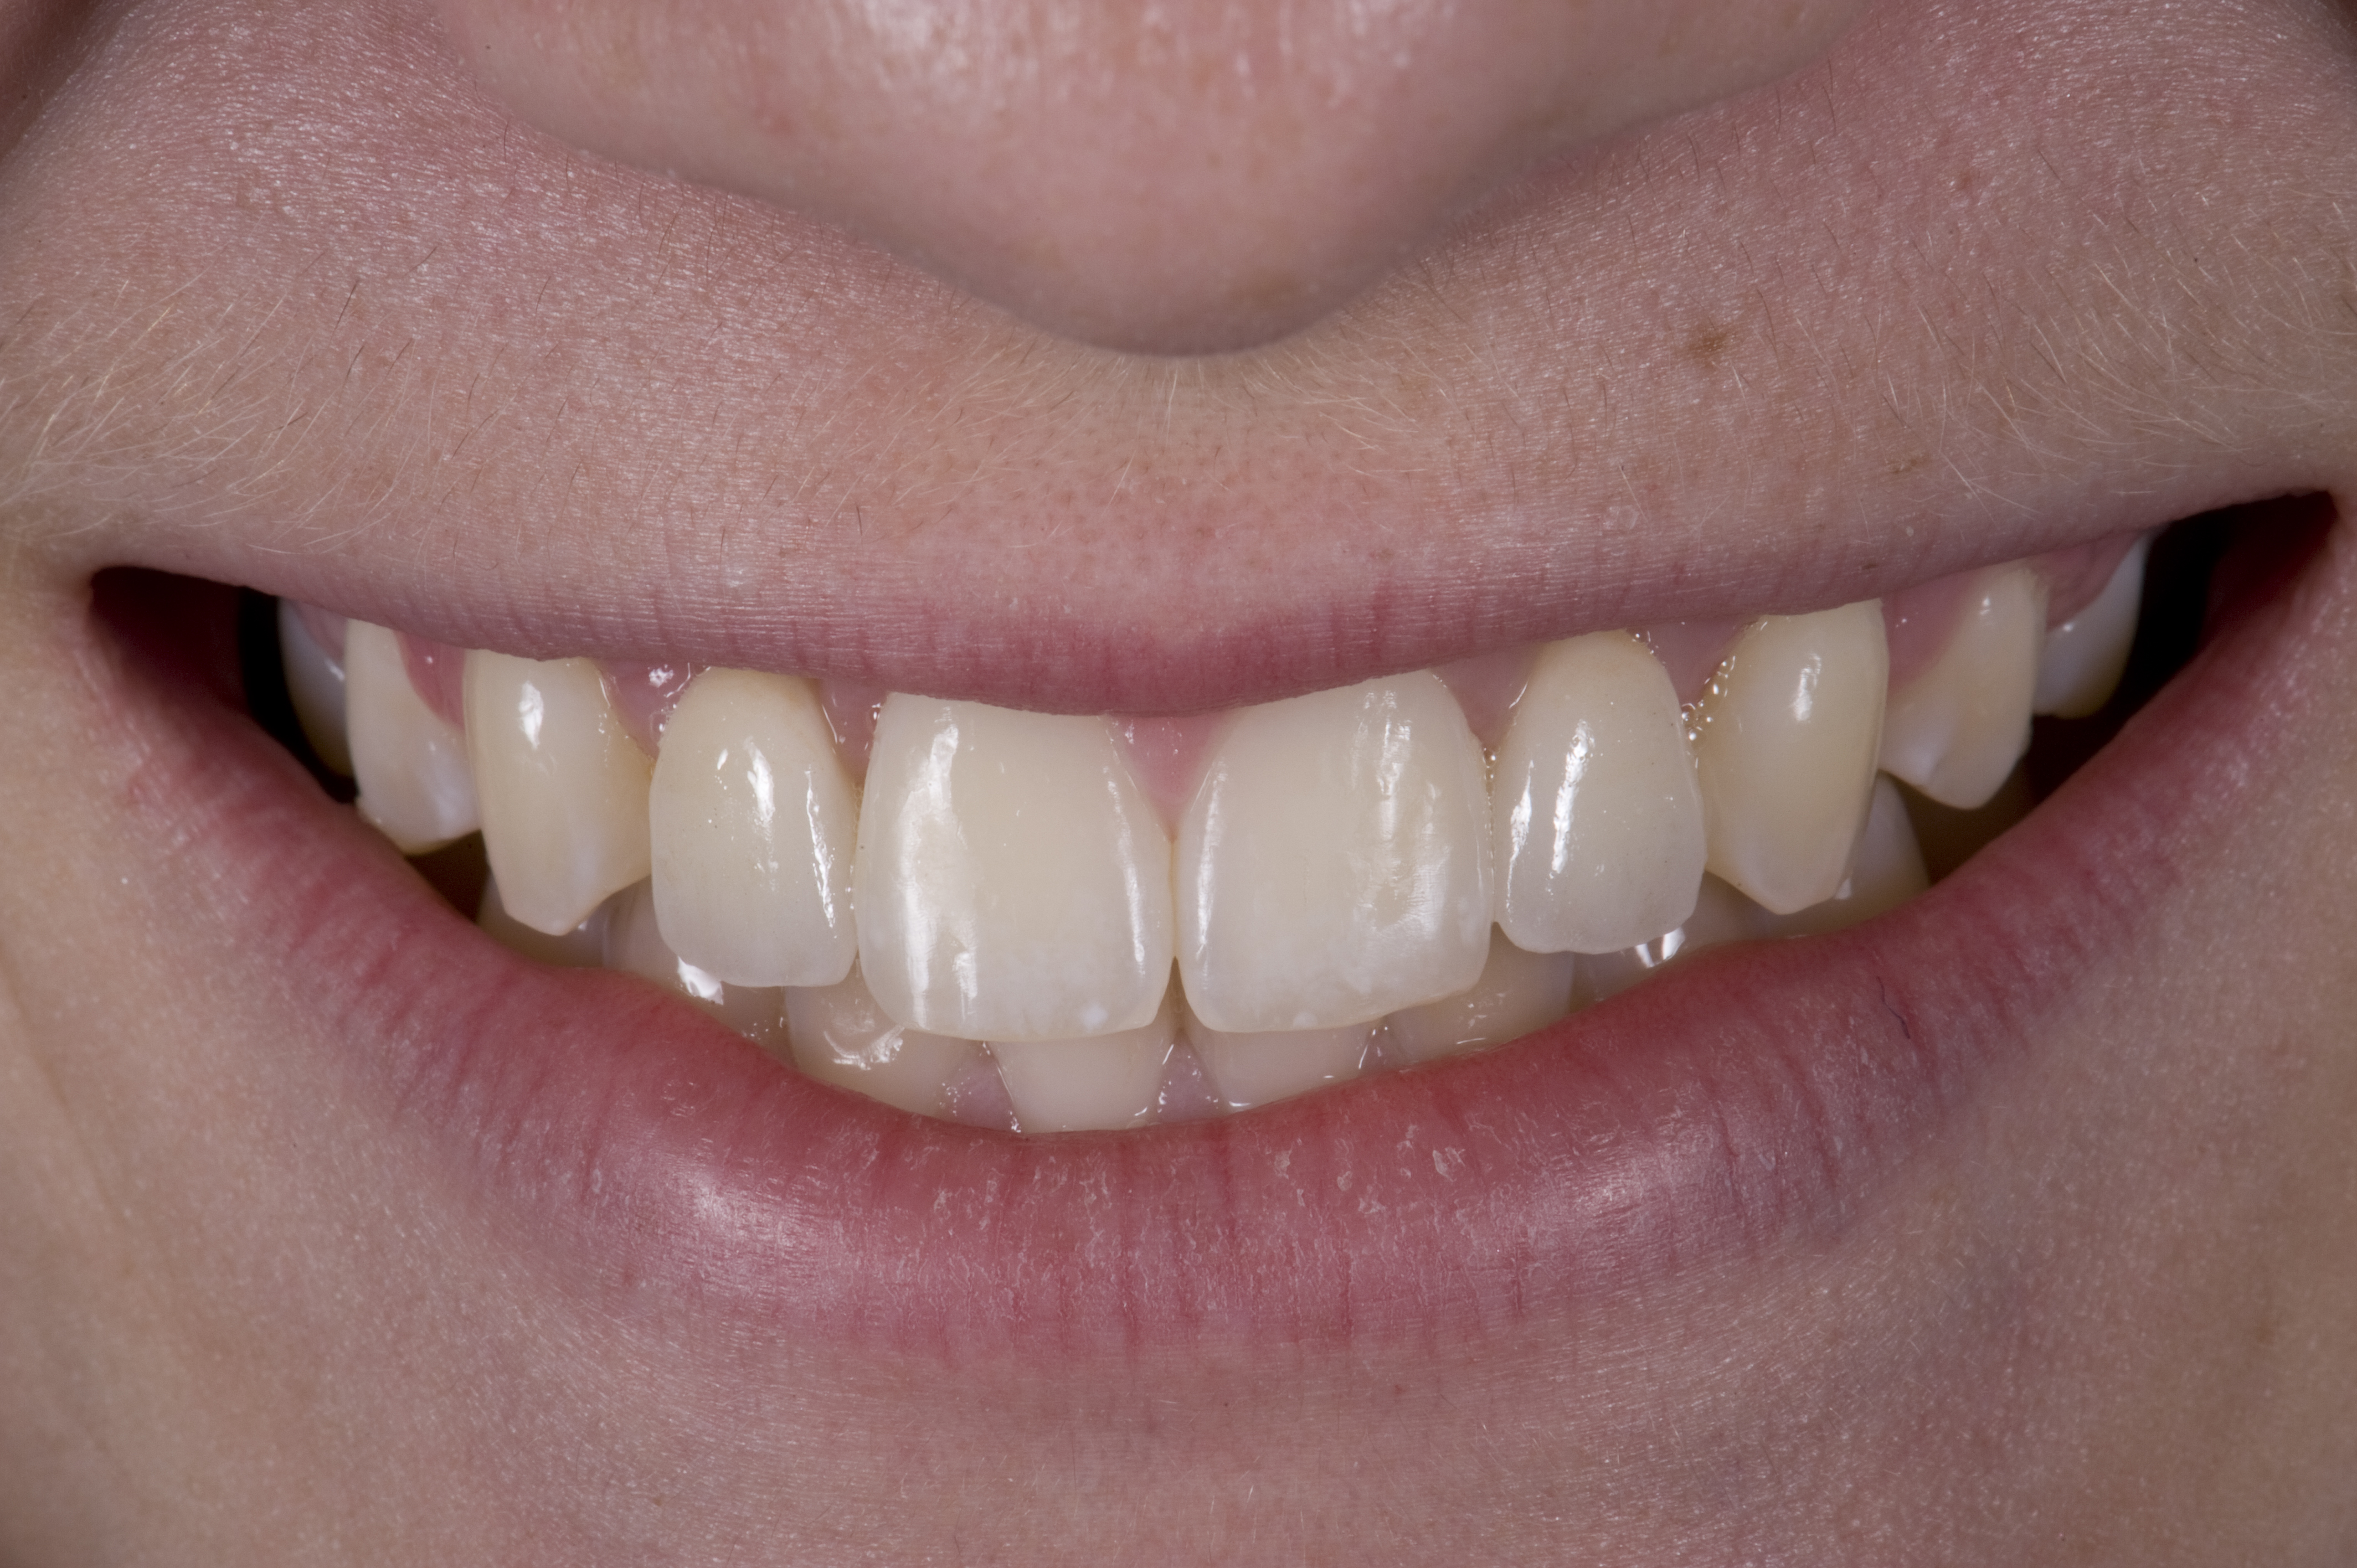

Case Presentation 2: Patient Does Not Want to Have an Implant Placed

Some patients do not want an implant due to the need for surgical intervention, and others may not have enough space for implant placement. A 15-year-old patient presented to the office after completion of orthodontic treatment to idealize the spacing of her teeth and improve her occlusal relationship (Figure 12 through Figure 14). Because both of her maxillary lateral incisors were missing, the patient was wearing a retainer with lateral incisor pontics. She had a busy school schedule, but expressed her desire for a fixed restorative option. All of her options were discussed, and the patient was informed that if she wanted an implant, she would have to wait for at least 3 to 4 years for completion of growth. The patient was not sure if or when she wanted to have an implant placed in the future, especially considering her busy schedule and desire to attend college after high school. Considering her age and the need to be conservative, a single-wing zirconia Maryland Bridge was chosen as the ideal prosthetic replacement option. Because bonding a non-etchable and smooth surface such as zirconia requires chemical adhesion, it was decided to use a modified technique to make the bridge more retentive. One of the ways to improve adhesion of a zirconia bridge is to use an etchable feldspathic ceramic layer on the internal surface of the zirconia retainer.56-58 Unfortunately, it can be difficult to determine the thickness of the ceramic and ensure accurate seating of the restoration.

(12.) 15-year-old girl after orthodontic therapy idealized maxillary lateral incisor spaces.

Figure 12